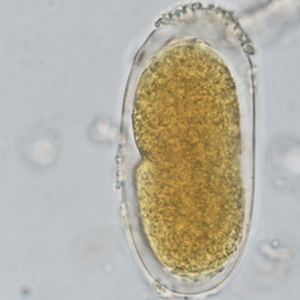

Les œufs de strongle présentent globalement la même morphologie ; ce sont des œufs ovalaires, à paroi lisse, possédant une morula et des faces latérales non parallèles. Leur taille est très variable (40 x 60 μm à 110 x 230 μm) et les groupes évoqués ci-dessus peuvent présenter des caractéristiques permettant d’orienter le diagnostic mais ces dernières sont à prendre avec précaution. Ces œufs, lorsqu’ils persistent longtemps dans le milieu extérieur, peuvent présenter un embryon vermiforme (Garcia, 2021).

- Les anguillules(Strongyloides): ces nématodes rentrent dans le diagnostic différentiel des œufs de strongle embryonnés. A l’inverse des œufs de strongles, ils mesurent 40-70 μm de longueur pour 20-35 μm de largeur, possèdent une paroi très fine et leurs faces latérales sont parallèles (Garcia, 2021).

- Les acariens: les œufs d’acarien sont plus gros que la plupart des œufs de strongles (100-140 μm de longueur pour 50-80 μm), ils présentent également un contenu granuleux, avec de nombreuses vacuoles nutritives. Lorsque l’embryon est développé, il prend une forme caractéristique d’acarien (Petithory et al., 1995).